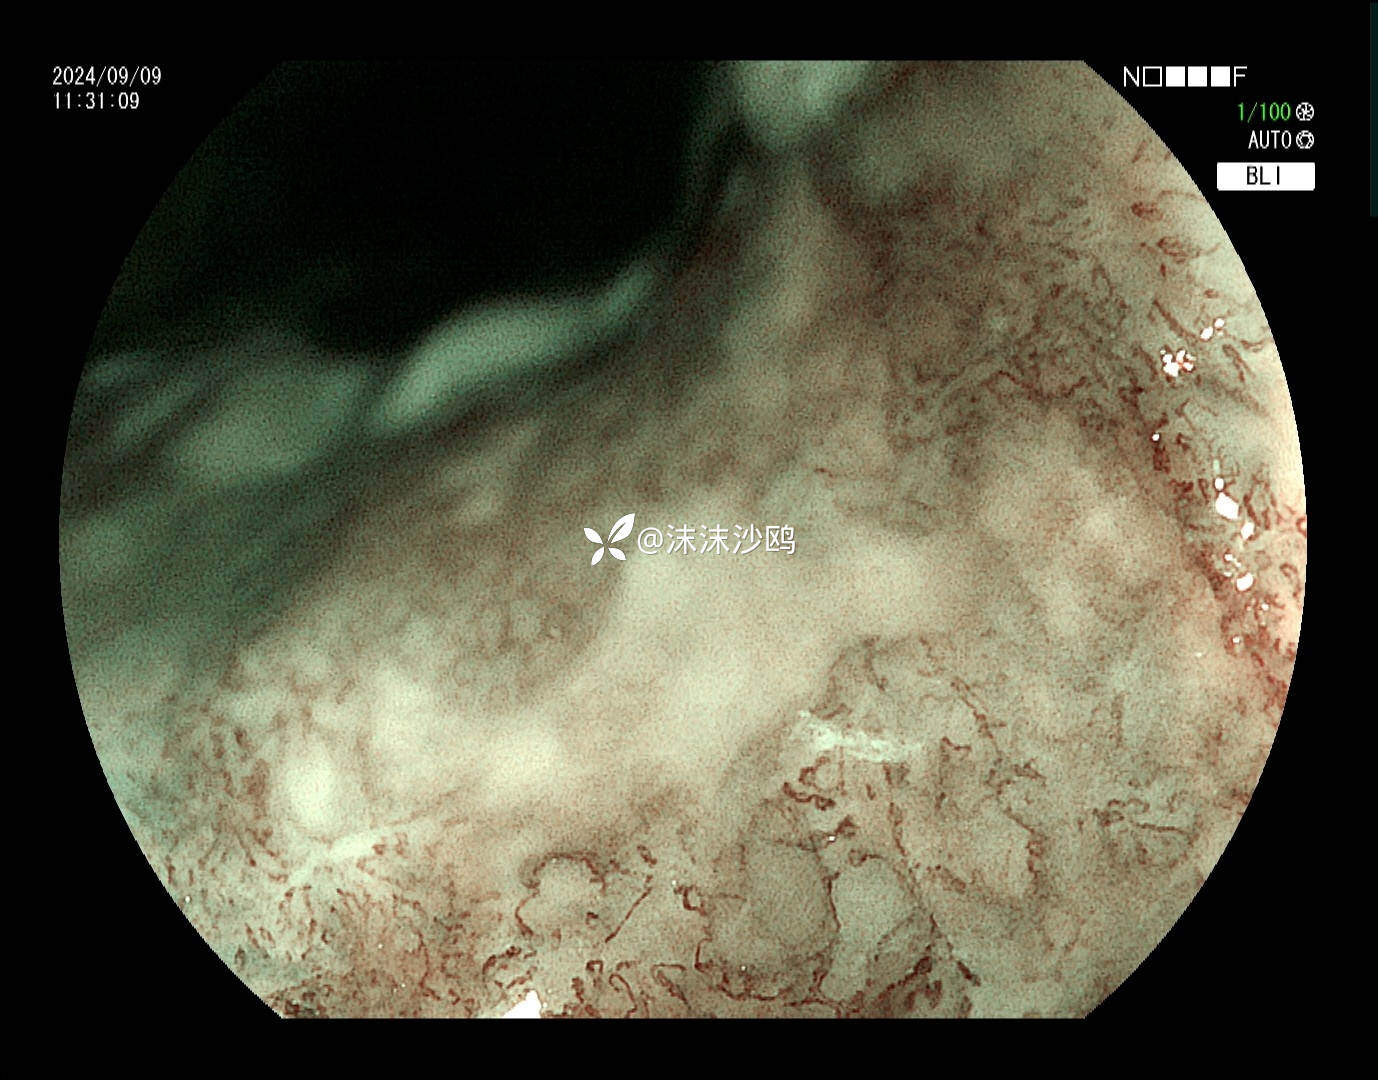

BLI

ME

该患者平素无明显症状,吸气注气观察病灶延展性,柔软度可,白光观察粘膜呈现发红粗糙,BLI放大观察呈现明显茶褐色,可见B1型血管,局灶可见紊乱生长的B2型血管,并见AVA区域,感觉小于0.5mm。镜下考虑浸润深度,不超过SM1,应该有内镜下D的可能性。等病理结果,希望符合内镜诊断。